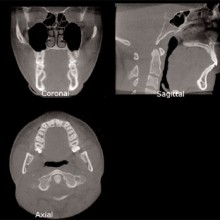

A tremendous amount of anatomic information is contained within the voxel volumes, and this information can be retrieved, analyzed, and viewed at a computer workstation using visualization and/or analytic software. The computer monitor is a two-dimensional, eight-bit display used to visualize three-dimensional, twelve-bit image data. The twelve-bit data can be viewed on an eight-bit display by using the technique of windowing, which allows for visualization of the entire 4096 shades of grey; eight bits at a time. Often, the anatomic volumes are acquired as voxel layers, and stacked as a series of parallel cross sections of the anatomy. These stacks can be displayed and viewed as a series of two-dimensional cross sections by sequentially paging through them in orthogonal planes (sagittal, axial, coronal). This is called multiplaner reformatting (MPR). MPR is the two-dimensional display of three-dimensional data in multiple projection planes (Figures 2a, 2b). Spatial relationships between three simultaneous displayed planes are communicated by projecting one plane onto the corresponding orthogonal planes as lines. Since the anatomic structures of interest occupy multiple layers within a stack, the clinician needs to perform a mental reconstruction of the anatomy. Coronal, sagittal, and axial views can be linked with synthesized views, such as oblique and/or curved slices or slabs. Slices or slab thickness can be manipulated directly and in real-time. The volume or slab of image data can be viewed with different modes of display, including MIP, SSR, and VR.